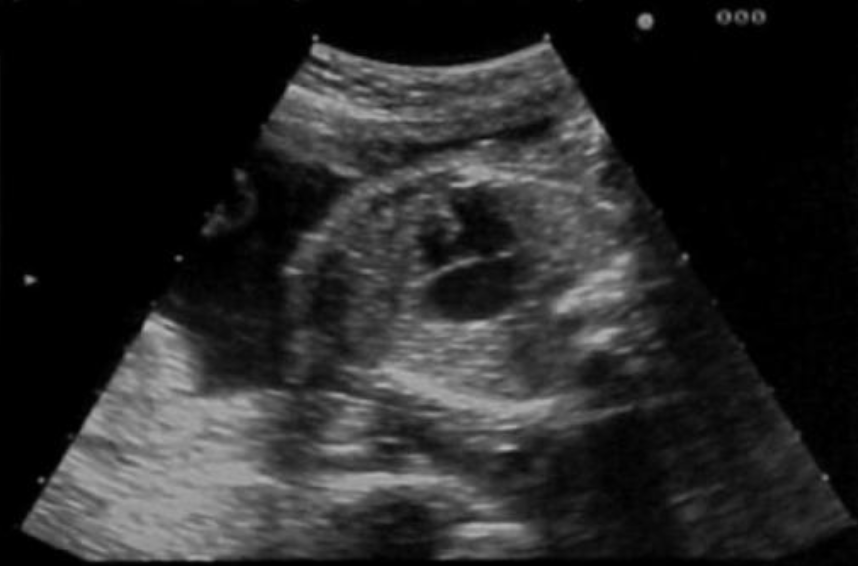

a) type 1 congenital cystic adenomatoid malformation

b) diaphragmatic hernia left side

c) diaphragmatic hernia right side

d) left lung agenesis